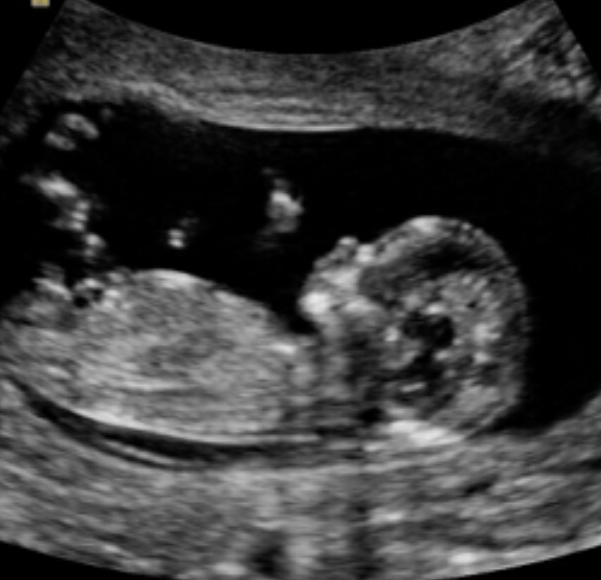

Была сегодня на первом скрининге. Я в восторге!!! Отличный врач (Авраменко), есть второй экран, где видно ребёночка, включил послушать сердечко. Что удивило - срок у нас 11,4 с даты последних м, а по развитию мы 12,2. Круто!!! Пол не сказали, да я и не спрашивала. А вот у матки наконец то тонус спал, ураааа! Угрозы больше нет, можно чпокаться)))